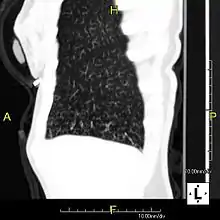

| Sagittal reformatted CT image showing "tree in bud" appearance of impacted distal small airways in primary ciliary dyskinesia | |

In radiology, the tree-in-bud sign is a finding on a CT scan that indicates some degree of airway obstruction.[1] The tree-in-bud sign is a nonspecific imaging finding that implies impaction within bronchioles, the smallest airway passages in the lung. The differential for this finding includes malignant and inflammatory etiologies, either infectious or sterile. This includes fungal infections, mycobacterial infections such as tuberculosis or mycobacterium avium intracellulare, bronchopneumonia, chronic aspiration pneumonia, cystic fibrosis or cellular impaction from bronchovascular spread of malignancy, as can occur with breast cancer, leukemia or lymphoma.[2] It also includes lung manifestations of autoimmune diseases such as Sjögren syndrome or rheumatoid arthritis.[3][4]

Histopathologic studies have shown that the tree-in-bud pattern is caused by demarcation of the normally invisible branching course of the peripheral airways, which usually results from bronchioles being plugged or blocked with mucus, pus or fluid. In addition, dilated and thickened walls of the peripheral airways and peribronchitis can make the affected bronchioles more easily visible, as is seen in patients with cystic fibrosis.